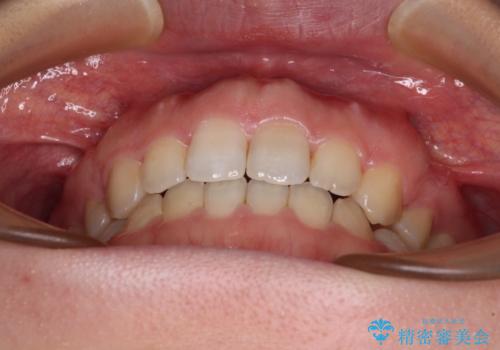

治療は順調に進み、予定された期間で終了することができました。

装置除去後には、スッキリとした口元となり、大変満足していただきました。